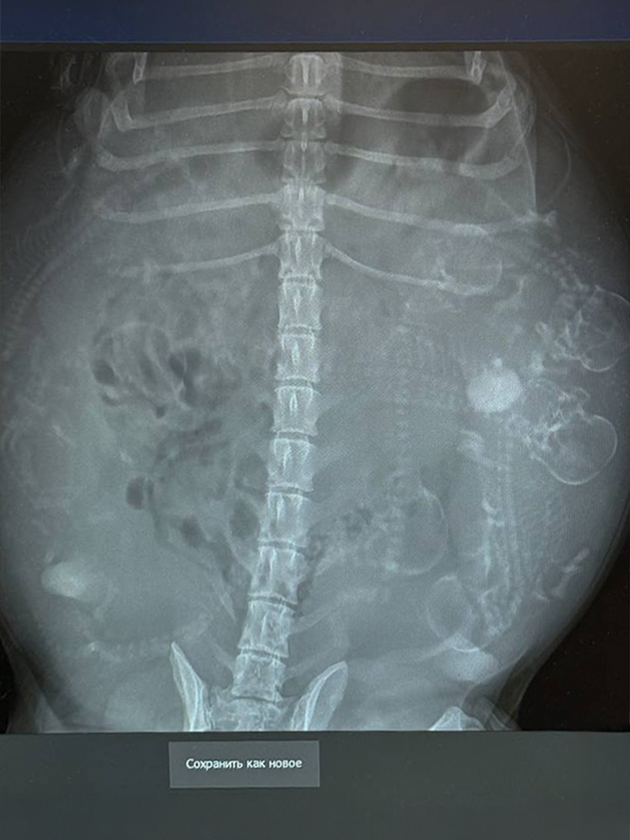

Чтобы подтвердить беременность у собак, с 21—25-го дня после предполагаемой овуляции или вязки ветеринары проводят УЗИ брюшной полости. А ближе к концу беременности — после 45-го дня — обычно делают рентген, чтобы посчитать щенков.